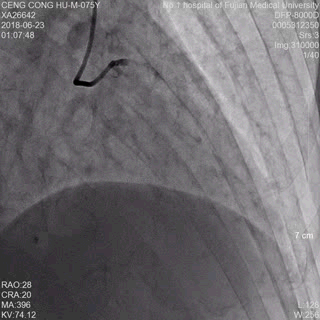

术前冠脉造影提示前降支远端急性闭塞 术后冠脉造影提示前降支血流通畅

患者曾老先生75岁高龄,当夜23:00突发胸痛,到达古田县医院急诊科时已面色苍白、大汗淋漓。古田县医院胸痛中心团队通过询问病史、急描床边心电图和床旁快速检测肌钙蛋白,确诊曾老先生罹患急性心肌梗死。我院胸痛中心团队与古田县医院转诊医师全程保持密切联系,动态关注患者转运情况,根据已有病情资料,决定绕过急诊科,启动急诊经皮冠状动脉内介入治疗(PCI)程序。20分钟内,介入团队彭峰副主任医师、陈鑫医师、蔡瀚医师、陈忠灿护师均已快速到达介入室,等候患者的到来。00:55,疾驰的古田县医院救护车抵达我院,在彭峰娴熟的手术操作下,01:15分即成功为患者开通了“罪犯”血管。术后转入我院心内科病房观察,48小时后,曾老先生病情稳定,由我院转诊回古田县医院心内科继续治疗。